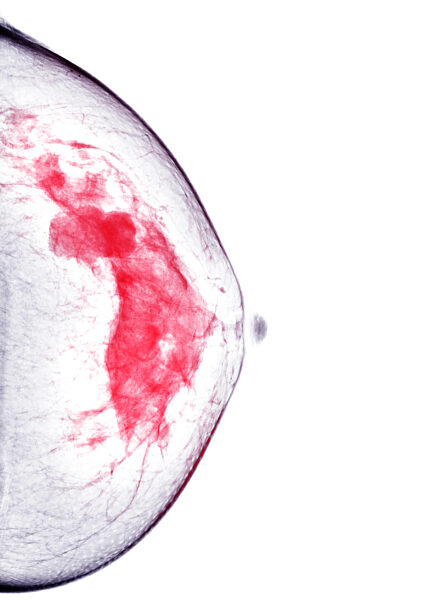

01.01.1000 - Coloured breast X-ray (mammogram) showing a BI-RADS (Breast Imaging Reporting and Data System) categorisation score of 5. A BI-RADS score of 5 is highly suggestive of a malignant (...

560491748

01.01.1000 - Coloured breast X-ray (mammogram) showing a BI-RADS (Breast Imaging Reporting and Data System) categorisation score of 5. A BI-RADS score of 5 is highly suggestive of a malignant (...

560492261